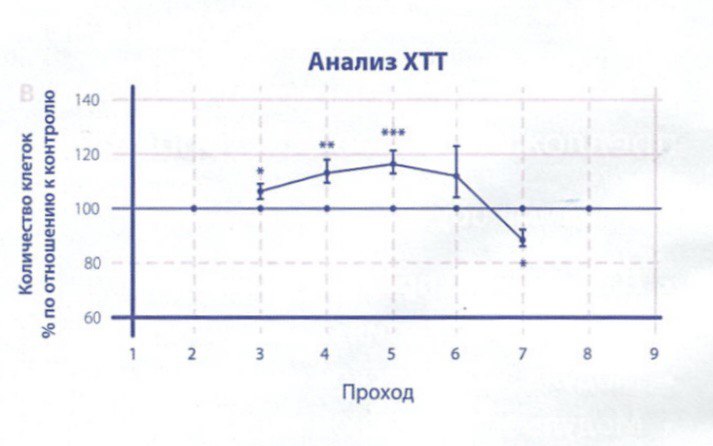

В результате стимуляции радиочастотными волнами начинается процесс регенерации тканей. Это может включать в себя увеличение производства коллагена и эластина, укрепление мышц и связок, а также уменьшение воспаления и отечности.

Нагревание тканей при помощи радиочастотных волн стимулирует биологические процессы в организме. Оно активизирует метаболизм, улучшает микроциркуляцию крови и лимфодренаж, а также стимулирует клетки к более активной работе.